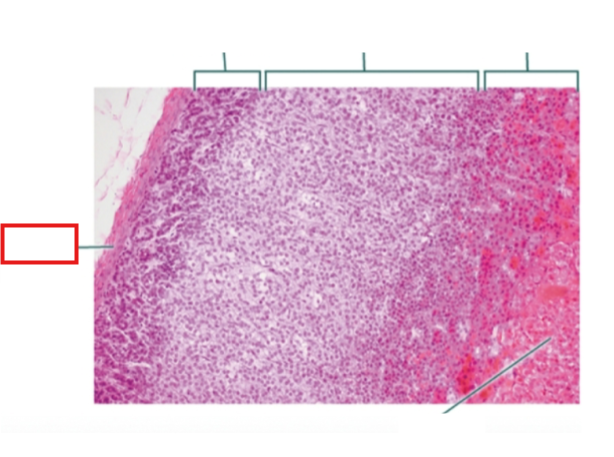

What structure is highlighted?

zona glomerulosa

What structure is highlighted?

zona fasciculata

What structure is highlighted?

zona reticularis

What structure is highlighted?

Capsule

What structure is highlighted?

medulla

What structure is highlighted?

capsule

What structure is highlighted?

zona glomerulosa

What structure is highlighted?

zona fasciculata

What structure is highlighted?

zona reticularis

What structure is highlighted?

adrenal medulla

What tissue is shown?

adrenal gland